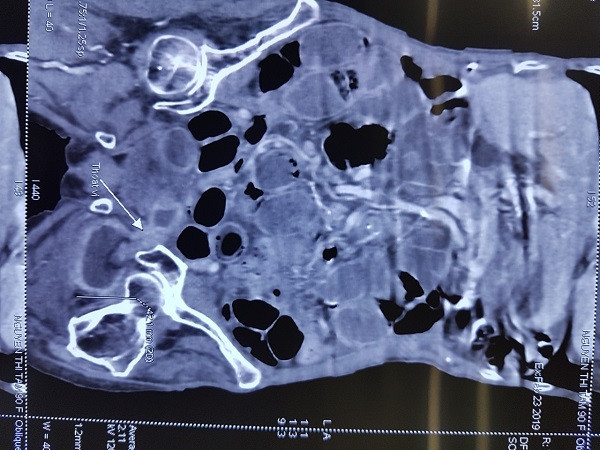

Hình ảnh chụp CT của bệnh nhân cho thấy thành ruột bị hoại tử, nhiều lỗ thủng

Qua thăm khám và chụp cắt lớp vi tính ổ bụng, bệnh nhân được chẩn đoán là tắc ruột do thoát vị bịt nghẹt bên trái ngày thứ 12, nghi đã có hoạt tử ruột gây áp xe hố bịt, nguy cơ phải cắt đoạn ruột. Vì thế, bệnh nhân được chỉ định mổ cấp cứu.

Quá trình mổ, sau khi giải phóng quai ruột nghẹt ra khỏi lỗ bịt, các bác sĩ thấy thành ruột của bệnh nhân đã bị hoại tử lỗ thủng đường kính 2cm, bờ mép nham mở mủn nát, đồng thời có dịch mủ chảy từ trong hố bịt trái.